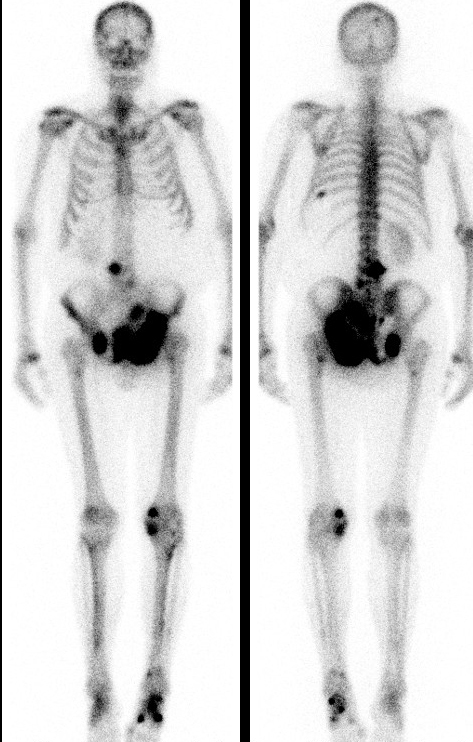

- une scintigraphie osseuse dont voici les images clés :

Question 11 : A l’issue de la consultation, vous envisagez :

Le TEP-scanner au 18-FDG n’a pas d’indication dans le bilan d’extension d’un cancer de prostate. Le scanner TAP combiné à la scintigraphie osseuse sont suffisants.

M. A. présente des localisations osseuses multiples, mais aucune localisation viscérale. Dans ce cas de figure, la castration par hormonothérapie (agonistes de la LH-RH avec prévention du flare-up) sera le traitement de première intention. L’ajout d’une chimiothérapie de type docétaxel se discute, mais il s’agit d’une discussion de spécialiste.